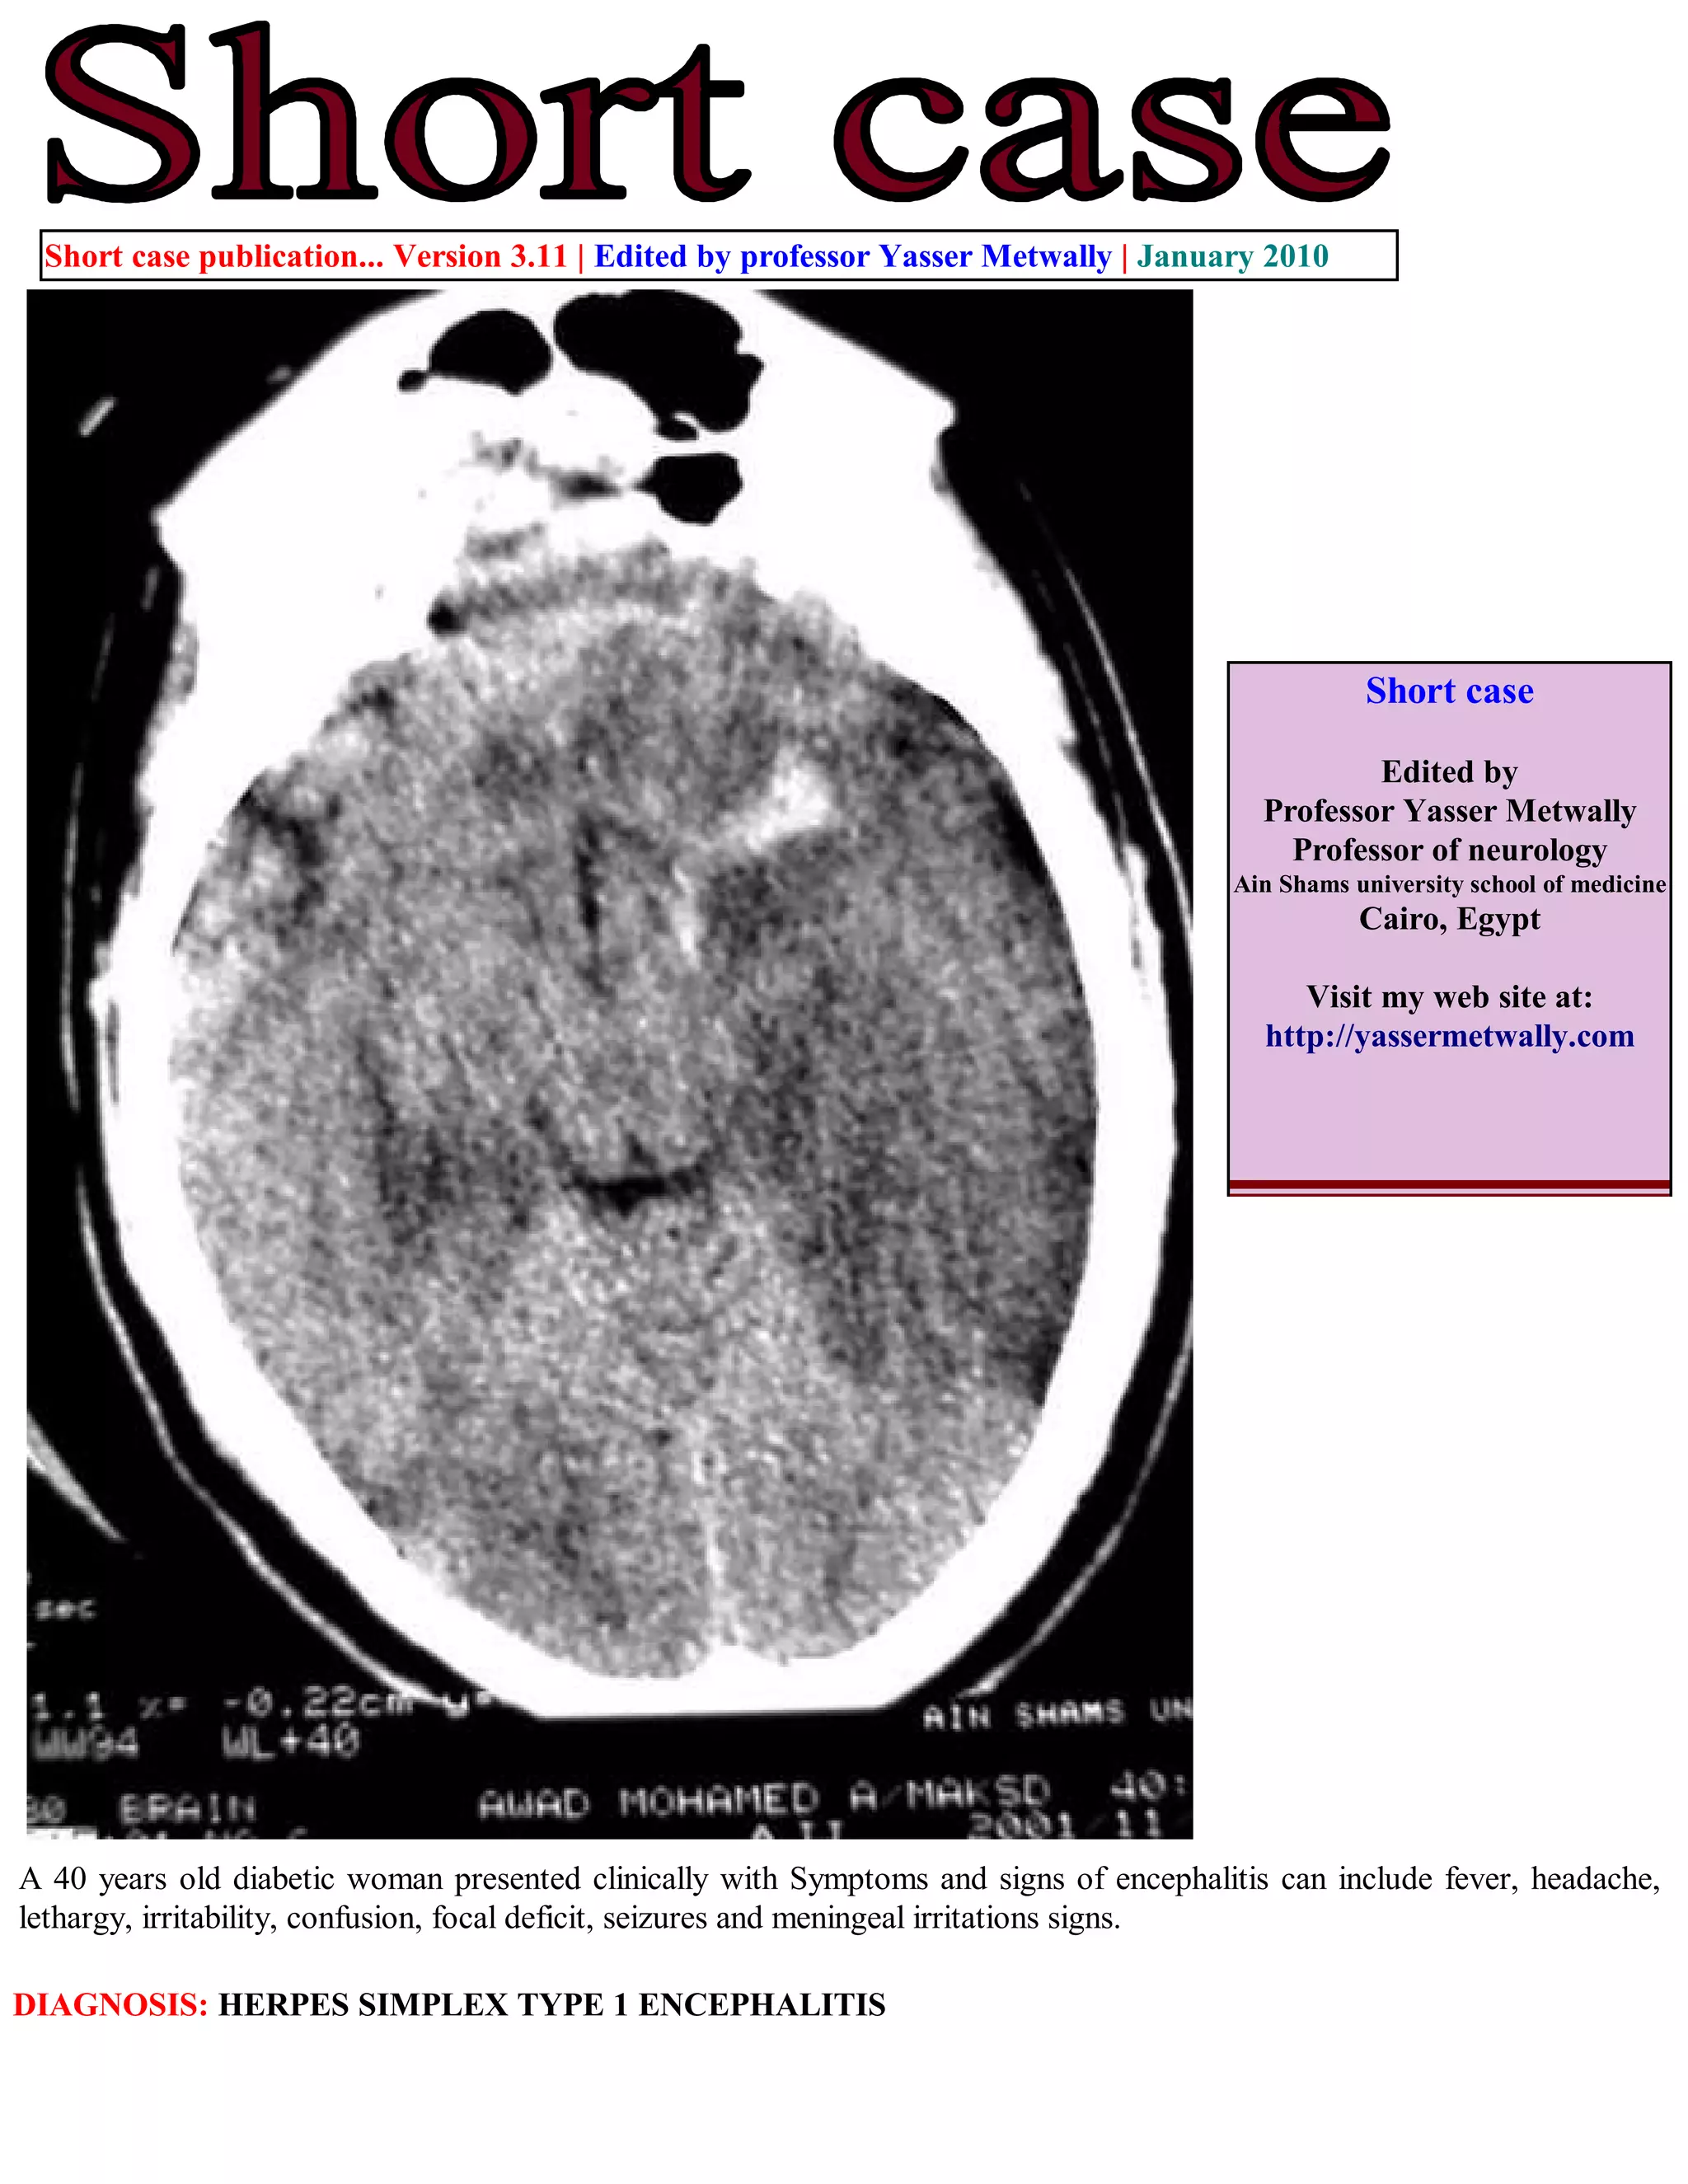

A 40 years old diabetic woman presented clinically with Symptoms and signs of encephalitis can include fever, headache,

lethargy, irritability, confusion, focal deficit, seizures and meningeal irritations signs.

DIAGNOSIS: HERPES SIMPLEX TYPE 1 ENCEPHALITIS

Figure 1. (A,B,C) A case of herpes encephalitis, precontrast CT scan. Notice the bitemporal, hypodensity, more in the left side.

Also notice insular, cingulate, and posterior orbital frontal hypodensities, more on the left side. A haemorrhagic component is

noticed at the left temporal lobe. The CT hypodensity represent vasogenic edema secondary to the associated vasculopathy.